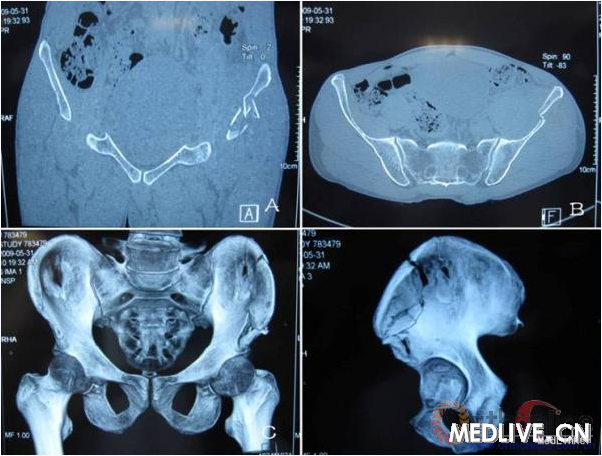

患者田某某,男,53岁,汉族,以“摔伤后左髂部疼痛肿胀3小时”为主诉入我院骨科住院治疗,经骨盆CT以及骨盆3D重建显示左髂骨翼骨折(见图1),临床诊断为左髂骨翼骨折。入院后给予保守治疗,卧床、制动,预防肺内及尿路感染。由于经济原因未予以华法林、利伐沙班等抗凝药预防治疗,6天后出院。回当地医院继续治疗,用促进骨愈合以及活血化瘀的中药,治疗期间左下肢较右下肢略肿胀,但未见明显肿胀。伤后20天在进行功能康复锻炼时突然出现胸痛、胸闷、呼吸困难,同时伴左下肢轻微肿胀(见图2),转入我院急诊抢救治疗。血气分析:PC02:33mmHg,P02:82.8mmHg;D-二聚体:20µg/ml;生化指标:AST:44U/L,LDH:257U/L,CK-MB:2.0u/L,TNI<O.5 µg/L;心电图:未见异常。肺动脉增强CT显示右肺中间动脉内见低密度影,造影剂充盈缺损,右肺中叶、双肺下叶及分支内均可见低密度影,部分分支内见少许造影剂显影。影像学诊断为双侧肺动脉多发栓塞,以双肺下叶动脉及右肺中叶动脉为著(见图3)。超声检查:左下肢股静脉内径约1.13cm,股浅静脉内径约0.63cm。股深静脉内径约0.7cm。腘静脉内径0.7cm,内见血栓样回声,未见明确彩色血流显示。超声诊断为左下肢深静脉血栓形成。给予低分子肝素钙(速碧林)0.4 ml每12小时皮下注射7天,吸氧,制动,同时华法林2.5 mg每日1次口服抗凝治疗,渐增量至3mg每日1次,定期检测监测凝血三项,国际标准化比值(INR)维持在2.5~3.0。由于患者经济原因,未行溶栓治疗、血栓抽吸及滤器的安装。治疗一周后患者胸痛、胸闷、呼吸困难等症状明显减轻,1个月后胸片示右下肺动脉及心影大小正常。